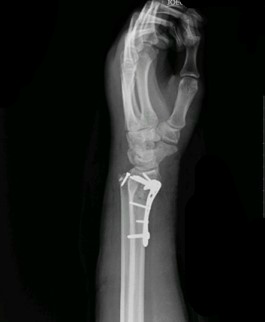

아랍에서 2013년 초 업무중 사고로 추락하여 요골원위부분쇄골절의 상해를 입었으며

국내로 이송되어 수술후 입원 3개월, 통원치료 2개월 시행하였으며

해외근재보험약관상 후유장해 12급,

맥브라이드방식에 따른 후유장해 13%를 판정받았습니다.